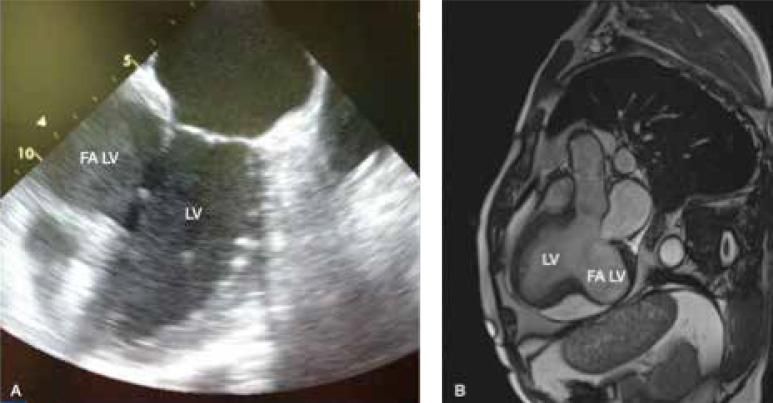

A large asymptomatic postinfarction left ventricular pseudoaneurysm - an incidental finding during a recurrent coronary event.

A large asymptomatic postinfarction left ventricular pseudoaneurysm - an incidental finding during a recurrent coronary event.一个大型无症状性心肌梗死后左心室假性动脉瘤——在一次复发性冠状动脉事件中偶然发现。